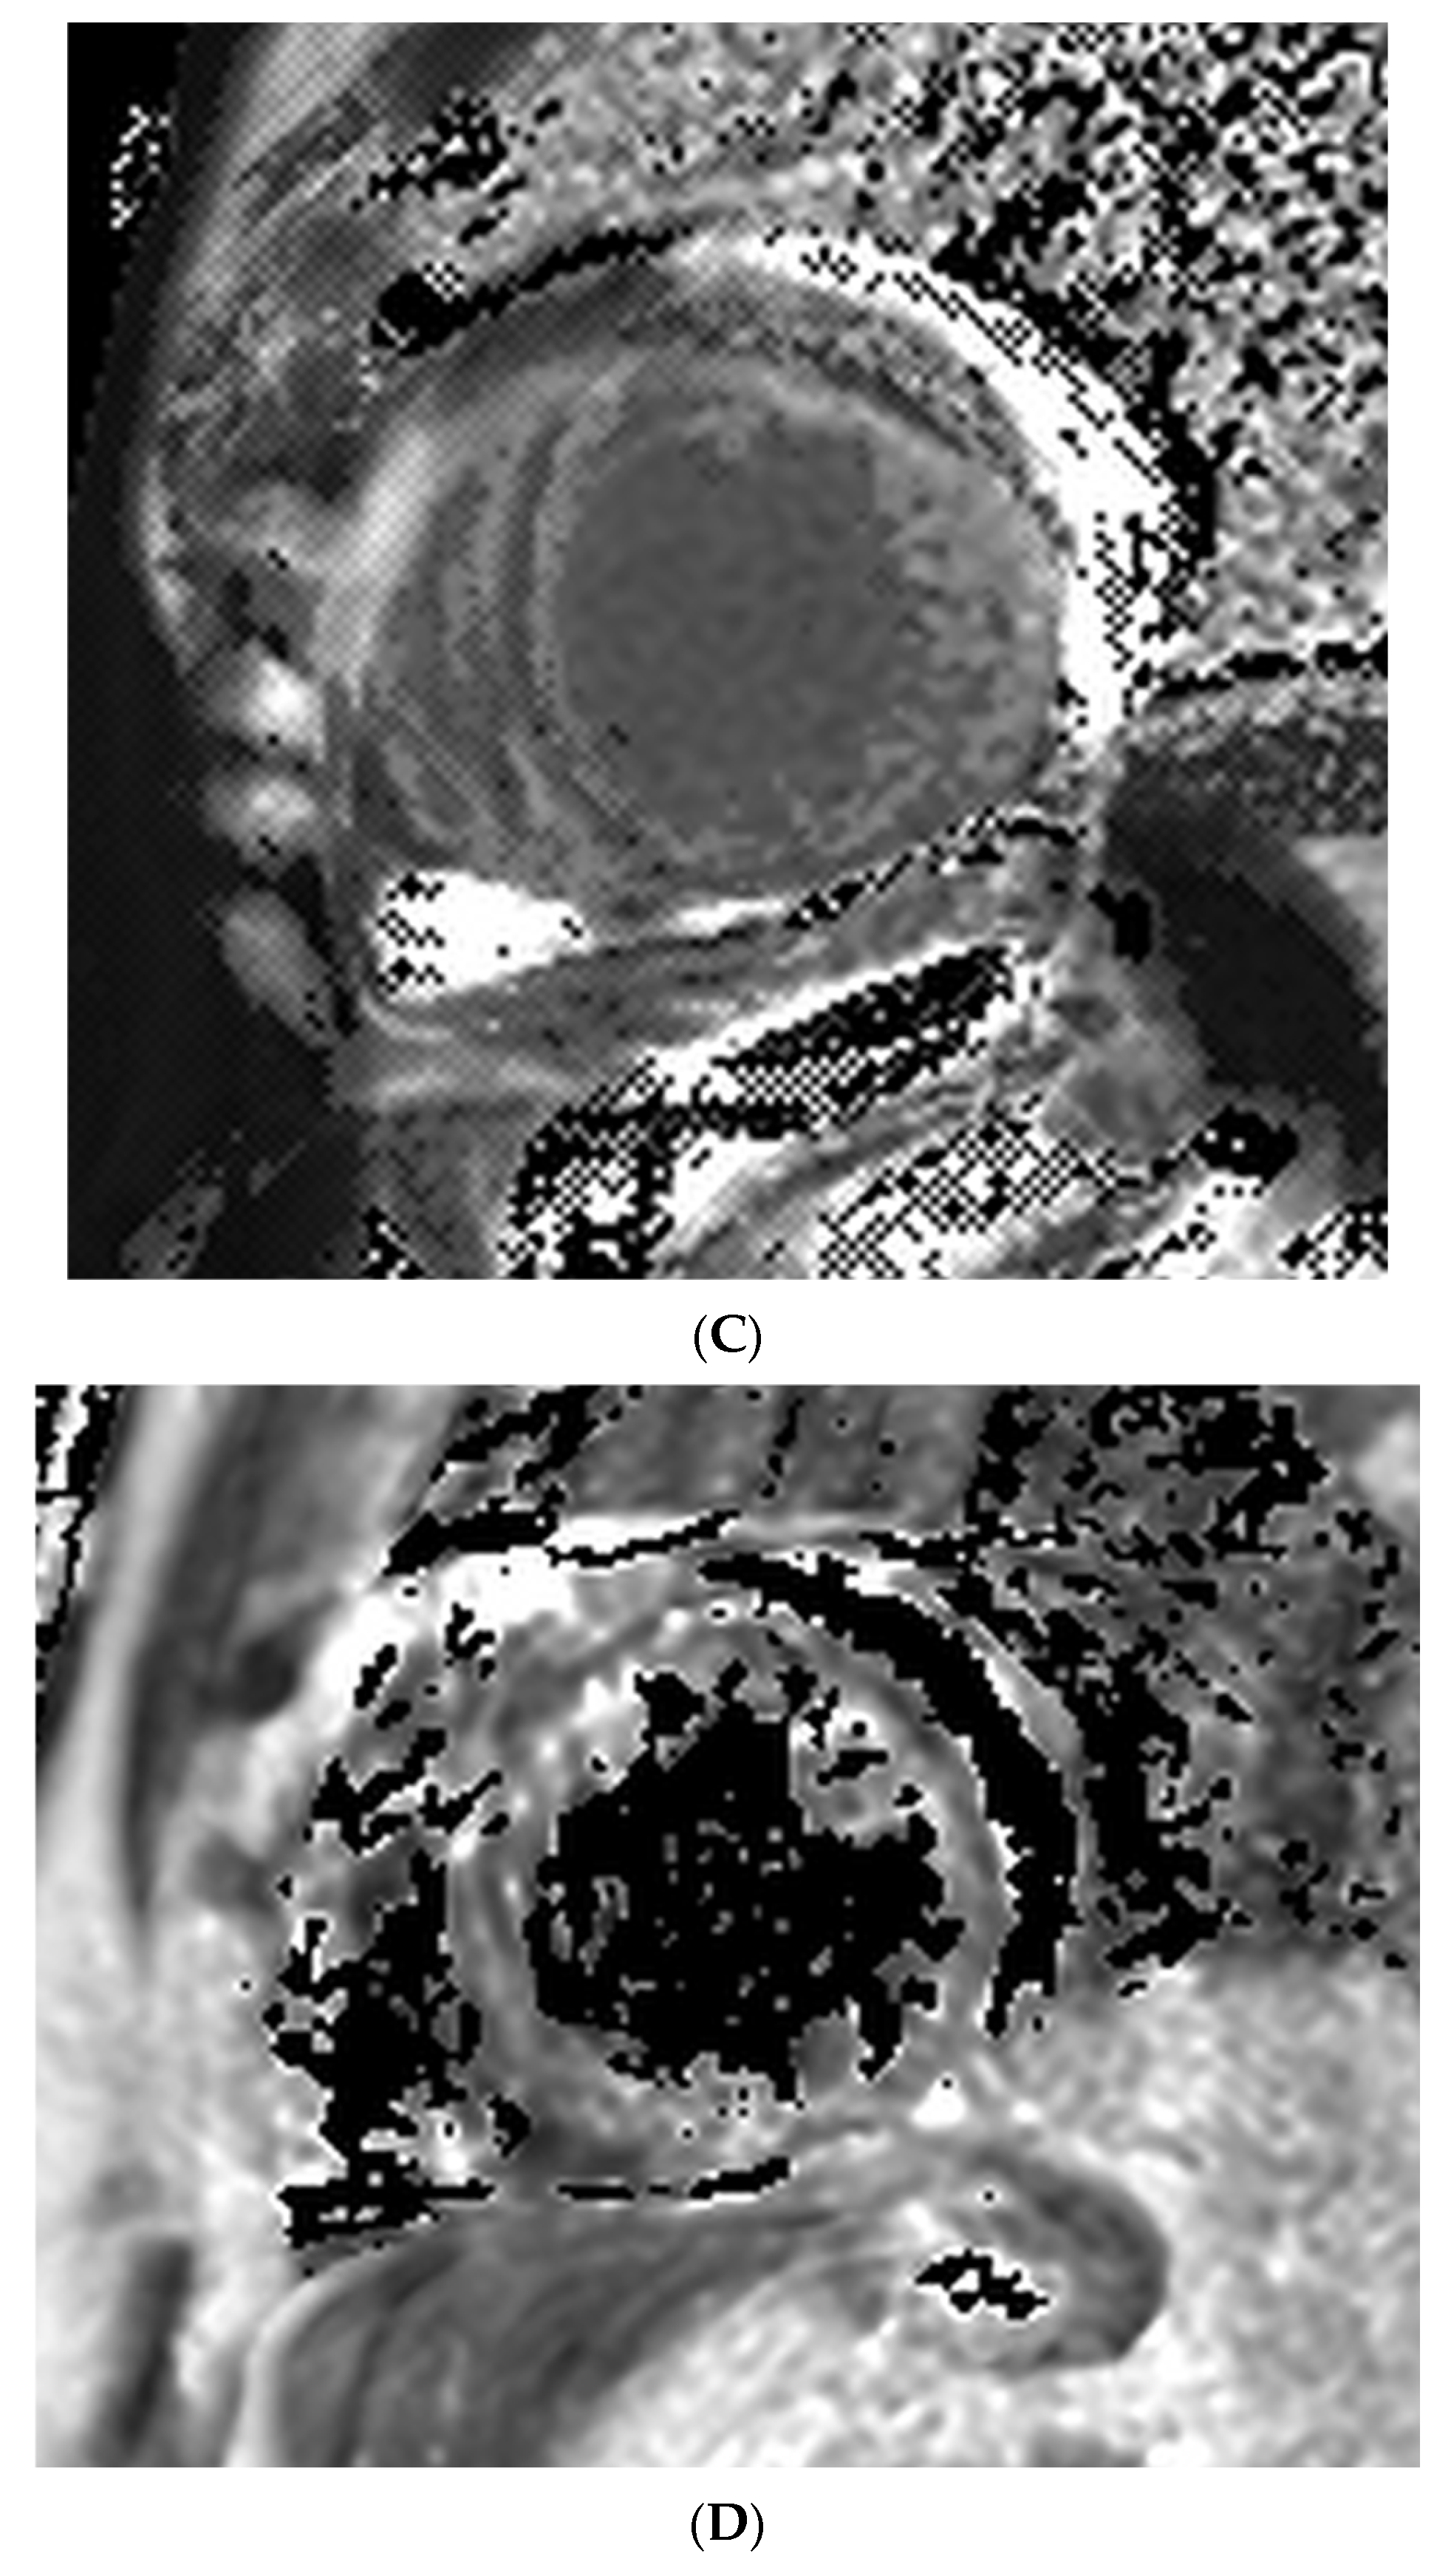

A 49-year-old male patient with a history of human immunodeficiency virus (HIV) was undergoing treatment for Kaposi sarcoma with cabozantinib and nivolumab (ICI) as the third line of treatment. Approximately 2 months after his last treatment, this patient presented to the emergency room with progressive shortness of breath over the last few weeks and was found to be in acute heart failure. An electrocardiogram showed sinus tachycardia with occasional premature ventricular complexes (Figure 2). The troponin I level peaked at 0.62 ng/mL (normal value < 0.03 ng/mL) and the B natriuretic peptide level was 1023 pg/mL (normal value < 100 pg/mL). The baseline echocardiogram prior to treatment initiation showed normal biventricular function, but his echocardiogram at presentation showed severely reduced left ventricular systolic function with an ejection fraction of 30% and a small pericardial effusion (Figure 3). Left heart catheterization demonstrated normal coronary arteries. Right heart catheterization demonstrated minimally elevated filling pressures and borderline cardiac output/index. An endomyocardial biopsy was taken, with pathology showing mild interstitial fibrosis, but no evidence of active myocarditis. Cardiac MRI showed linear mid myocardial LGE in the interventricular septum (Figure 4A) that corresponded with the areas of myocardial edema seen on the T2-weighted images (Figure 4B). There was also elevated native T1 map at 1470 ms (normal 1000 +/− 50 ms at 1.5T) (Figure 4C) along with elevated T2 mapping at 70 ms (myocardial edema suggested if T2 > 55–60 ms) (Figure 4D), and a small pericardial effusion. ECV was unable to be calculated due to an artifact on postcontrast T1 images. This case met the ICOS diagnostic criteria (Table 2, cTn elevation + diagnostic CMR (major criteria)). The patient was started on a pulse dose of corticosteroids for the treatment of presumed myocarditis with significant improvement in symptoms and was discharged home with a stable dose of steroids, as well as goal directed medical therapy for heart failure (beta blockers, ARNI, and SGLT2i). Nivolumab was discontinued. The patient was followed-up in the cardio-oncology clinic and, due to the resolution of symptoms, his steroid treatment was tapered over the next few weeks. During his follow-ups, he showed a complete resolution of clinical symptoms and was able to recover a good exercise tolerance, but unfortunately a repeat echocardiogram at 9 months after the initial presentation showed a persistently reduced ejection fraction.

Figure 4. (A) Cardiac MRI LGE images from the clinical patient. Cardiac MRI images showing linear midventricular LGE (red arrows) in the basal and mid interventricular septum, extending into the anterior and inferior LV segments. Globally reduced biventricular function (LVEF 29% and RVEF 42%). (B) Cardiac MRI T2-weighted images from the clinical patient. Cardiac MRI T2-weighted images. There is interventricular T2 enhancement (red arrow) consistent with edema. (C) Cardiac MRI T1 mapping images from the clinical patient. Cardiac MRI T1 mapping images revealed an elevated native T1 map at 1470 ms (normal 1000 +/− 50 ms at 1.5T). (D) Cardiac MRI T2 mapping images from the clinical patient. Cardiac MRI T2 mapping images revealed elevated T2 mapping at 70 ms (myocardial edema suggested if T2 > 55–60 ms).